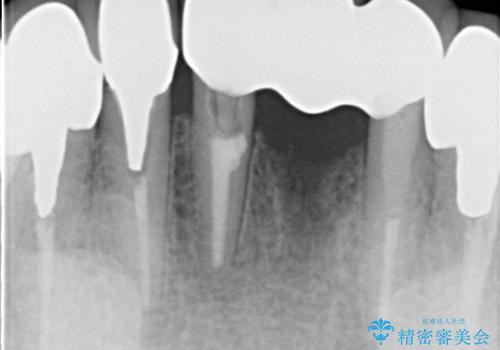

抜歯をしているため、その部位の治癒を待ってからブリッジを装着するので、2-3か月ほど治療期間を必要としました。